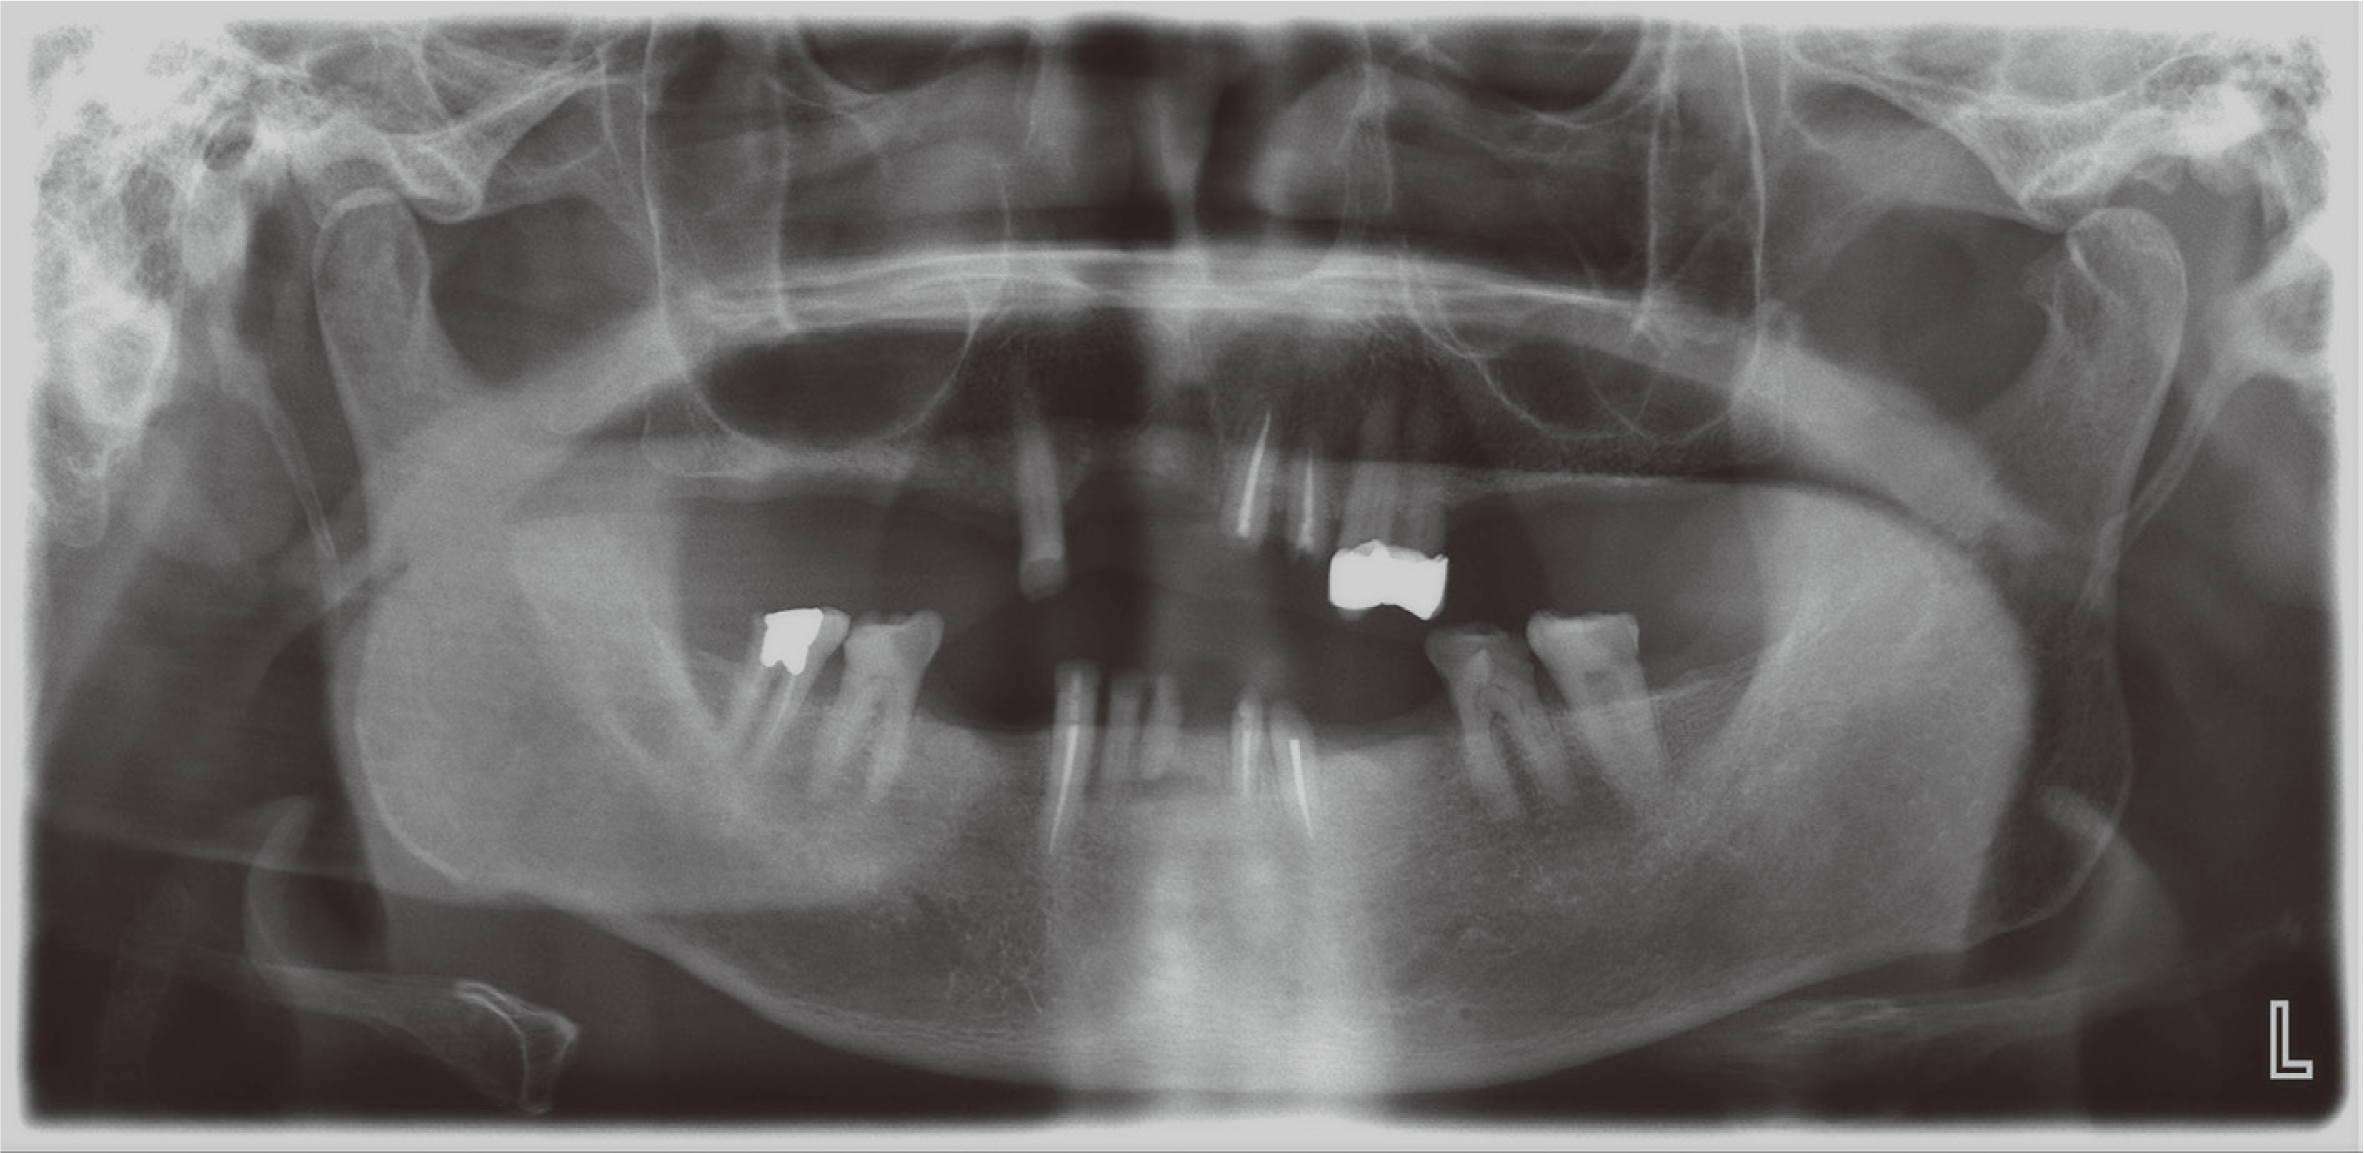

82세 남자로 다수 치아의 상실을 주소로 내원하였다. 의과력으로 고혈압, 당뇨 및 협심증 병력을 가지고 있었고, 특이할 만한 치과적 병력은 없었다. 파노라마 방사선사진 검사에서 다수의 치아 상실과 전반적인 치조골 소실을 보이나, 잔존한 치아 중 상악 양측 견치와 하악 대구치의 골지지는 양호하였으며, 대구치와 전치들의 치관파절이 있었다(Fig. 1). 좌측 턱관절에서 2016년에서 2020년까지 골변화가 의심되는 소견을 보였다. 그러나 턱관절의 통증과 불편감을 보이지 않았고 임상적으로 안정적인 턱관절 움직임을 나타내어, 적응된 턱관절 관계로 판단하여 보철치료 진행을 결정하였다. 구외 안모평가 시 발달된 저작근과 하악이 전돌된 안모를 가지고 있었다(Fig. 2). 구내 검사 시 습관성 폐구위에서 교합되는 치아가 없었으며 이에 따라, 잔존 치아들이 치조제 점막에 대합되어 뚜렷한 압흔이 관찰되었다(Fig. 3).

비가역성 하이드로콜로이드(Aroma Fine Plus, GC Co., Tokyo, Japan)를 이용하여 예비인상을 채득하여 진단모형을 제작하고, 중심위에서 알루왁스로 악간관계기록 채득 및 안궁이전을 시행하여 반조절성 교합기에 중심위 악간관계기록을 이용하여 부착하였다. 진단모형 분석 시 잔존 치근들은 지대치로 사용하기에 치질이 불충분하였으며, 그 외의 치아들도 전부관이 필요할 정도의 파절과 마모양상을 가지고 있었다(Fig. 4). 또한 구치부 지지를 상실한 전후방으로 엇갈린 교합상태를 보이며, 교합지지영역이 없는 Eichner’s index category C-1으로 분류되었다.8 Willis법을 이용한 안모분석비율과 교합안정거리(interocclusal rest distance) 측정 시 하안모가 짧았고 교합안정거리는 6 mm로 수직고경의 감소가 있다고 판단하였다(Fig. 5).